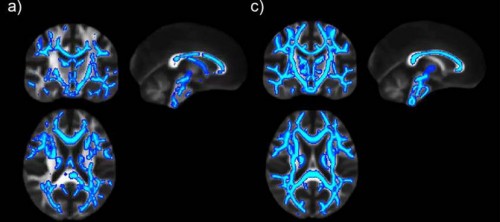

Esta imagen muestra que los daños cerebrales continúan tras seis semanas de abstinencia del consumo de alcohol. (Foto: INSTITUTO DE NEUROCIENCIAS)

“Con el consumo de alcohol se produce un cambio generalizado en la sustancia blanca, es decir en el conjunto de fibras que comunican distintas partes del cerebro”, precisa Canals. Las alteraciones son más intensas en el cuerpo calloso –relacionado con la comunicación entre ambos hemisferios– y la fimbria –que contiene las fibras nerviosas que comunican el hipocampo, estructura fundamental para la formación de memorias–.